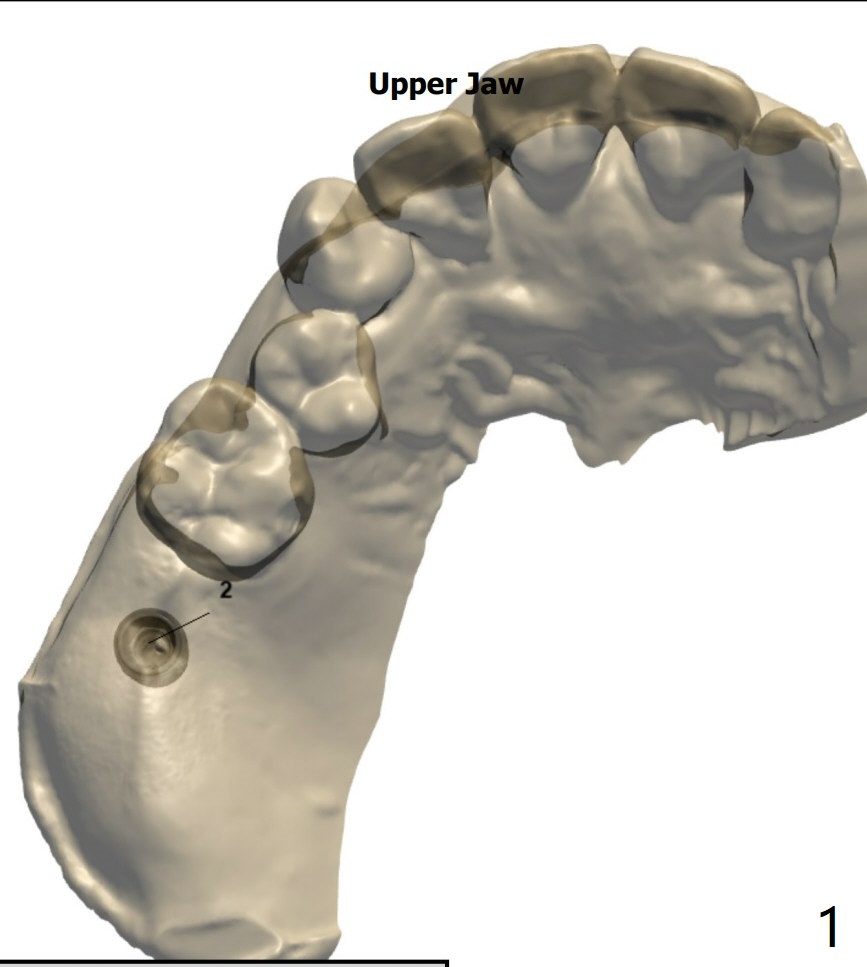

PRF,粘性骨粉用于上颌窦提升

Nearly 5 months post socket preservation. Prepare 4 mm Biopsy Punch. After light use of Tissue Punch to make mark in the gingiva, remove the guide, use the 4 mm Biopsy Punch to harvest the tissue and place the latter in PRF dappen dish. If implant torque is low, place bone graft over the implant, return the tissue to the site and use perio glue for fixation. Finally apply acrylic dressing. Prepare Sinus Approach Kit and 4x10 mm IS dummy implant.